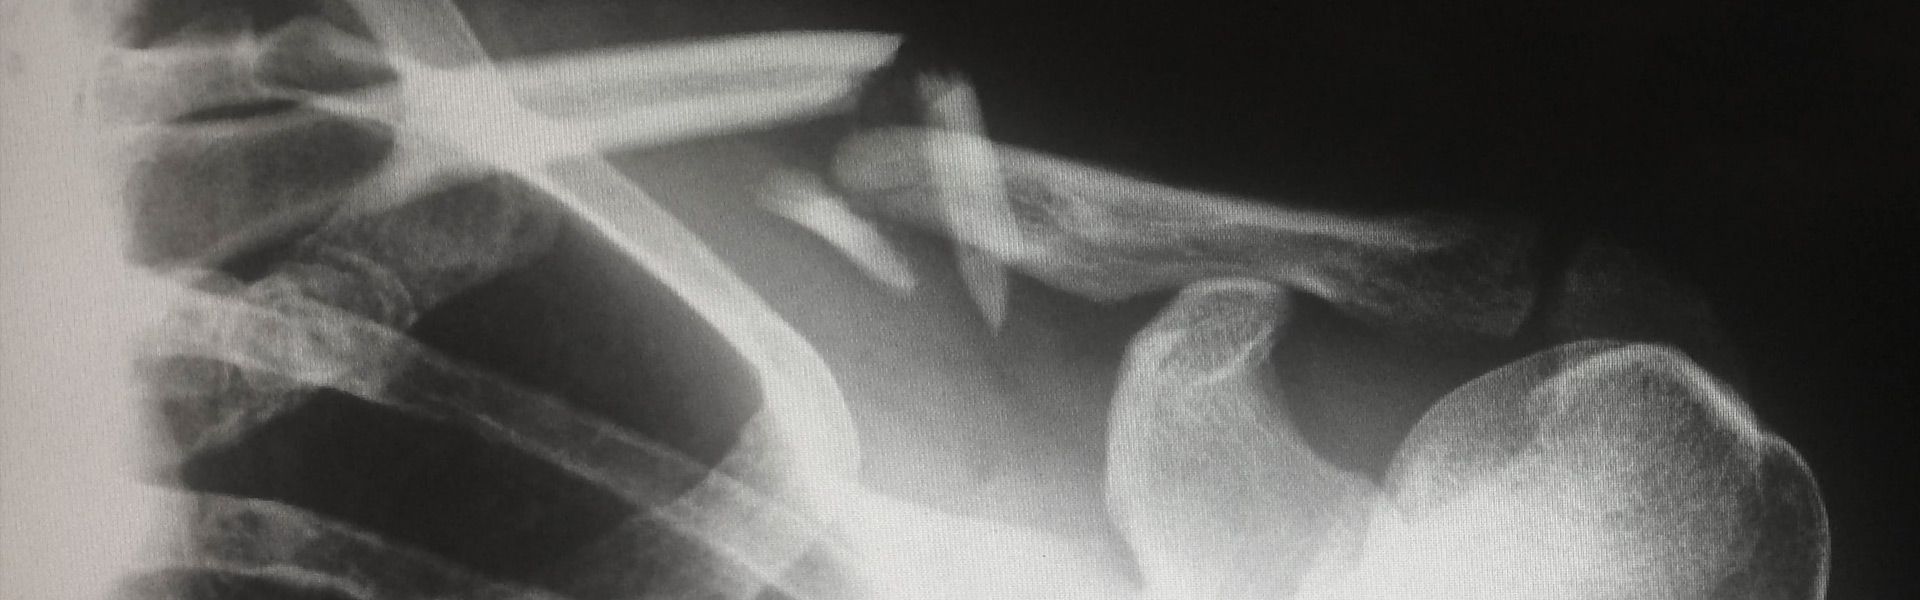

En esta clínica de traumatología y cirugía ortopédica en Santander, nos enfocamos en el tratamiento de casos de lesiones complejas en el hombro. Ofrecemos soluciones personalizadas para recuperar la movilidad y mejorar la calidad de vida de nuestros pacientes.

Recuperación en situaciones de lesiones complejas en el hombro

Contamos con un equipo de especialistas en traumatología que se dedica a proporcionar una atención integral y de alta calidad para casos de lesiones en el hombro que presentan desafíos adicionales. Utilizamos técnicas avanzadas y procedimientos especializados para asegurar una recuperación óptima.